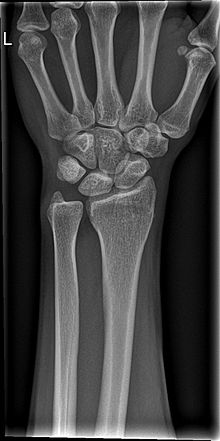

ПЕРЕЛОМ ЯКОЇ КІСТКИ І ЯКОЇ ЇЇ ЧАСТИНИ ВИ БАЧИТЕ НА РИСУНКУ?

варіанти відповідей

ДИСТАЛЬНОГО ДІАФІЗА

HUMERUS

ULNA

RADIUS

ПРОКСИМАЛЬНОГО ЕПІФІЗА

ДИСТАЛЬНОГО ЕПІФІЗА

ДІАФІЗА

МЕТАФІЗА